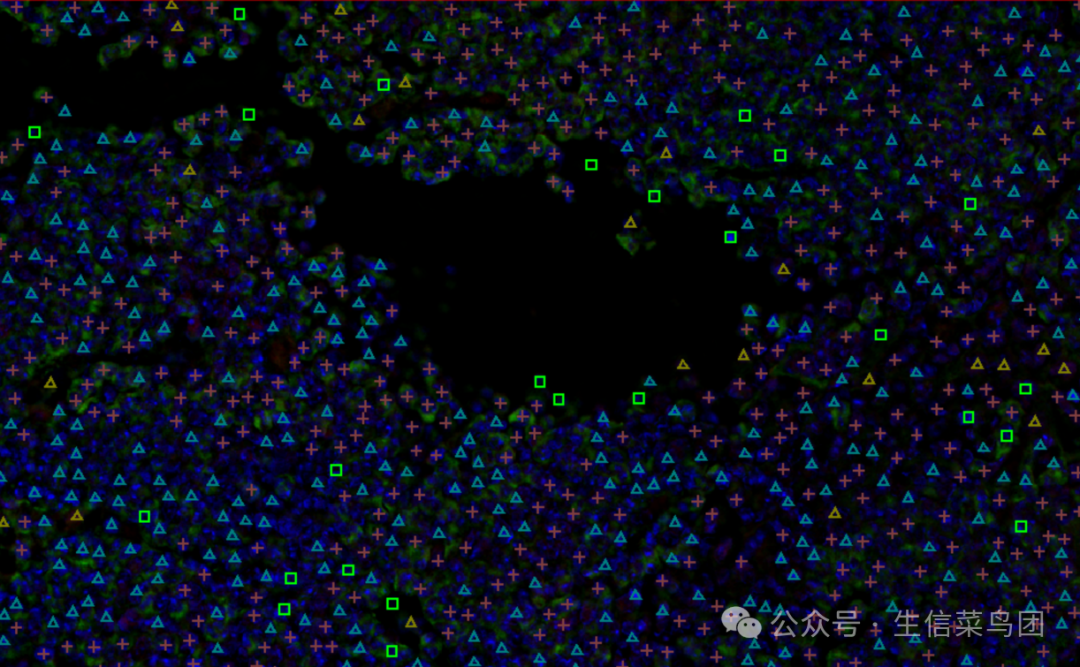

保存并运用以后,大功告成,我们得到了三阳性、双阳性的细胞,导出为结果即可开始分析啦

图片

也可以换一种表现形式